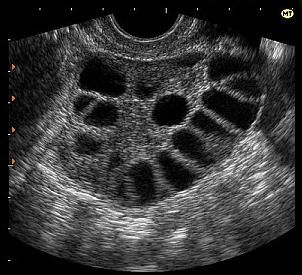

Синдром гиперстимуляции яичников (СГЯ) — редкое ятрогенное осложнение после стимуляции яичников (искусственная овуляция) с помощью вспомогательных технологий репродукции и других методов лечения бесплодия.

Симптомы СГЯ часто начинаются через 10 дней после инъекций и могут варьироваться от легкой до тяжелой формы, могут со временем ухудшаться или улучшаться.

Диагноз ставится на основании:

- Физического осмотра;

- Ультразвука. УЗИ покажет увеличение яичников;

- Анализа крови.

Симптомы СГЯ:

- Легкая/ умеренная/очень сильная боль в животе (внизу живота, а также в поясничном отделе);

- Вздутие;

- Сильная тошнота/рвота;

- Боль в пояснице во время месячных;

- Диарея;

- Сбивчивое дыхание;

- Внезапное увеличение веса более чем на 3 кг (вплоть до 15-20 кг) в течение 5-10 дней.